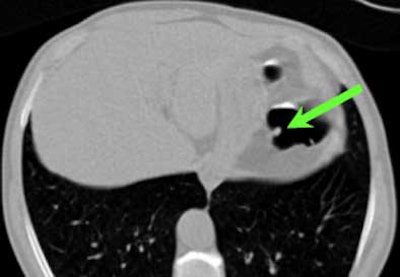

| Top to bottom: A 10-mm polyp in the splenic flexure can be seen in axial, sagittal, coronal, and 3D views. All images courtesy of Dr. Riccardo Iannaccone, University of Rome "La Sapienza." |